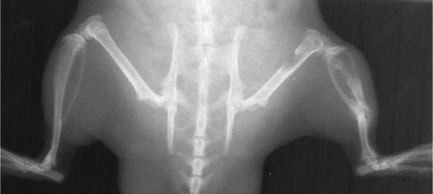

Researchers at Armbruster have succeeded in producing polyclonal anti-tumor-BSP antibodies in chickens, which resulted in the destruction of cancer cells in vitro as well as in animal models (see Fig. 1). Since chicken antibodies are not suitable for use in therapy for human patients, recombinant antibodies were identified that were produced from the HuCAL antibody collection Antibodies by Design. This technology provides a method to identify antibodies whose structure corresponds to human antibodies, which are therefore tolerated by the immune system.

X-rays of a nude rat show bone tumour after injection of tumour cells: After an average of 28 days, lytic metastases could be detected by X-rays; on day 35, the treatment with an anti-tumour-BSP antibody was started. Until day 60, the tumour resulted into a size of up to 40 mm2. Afterwards, the healing started and the tumour decreased its expansion to 25 mm2 (Day103).